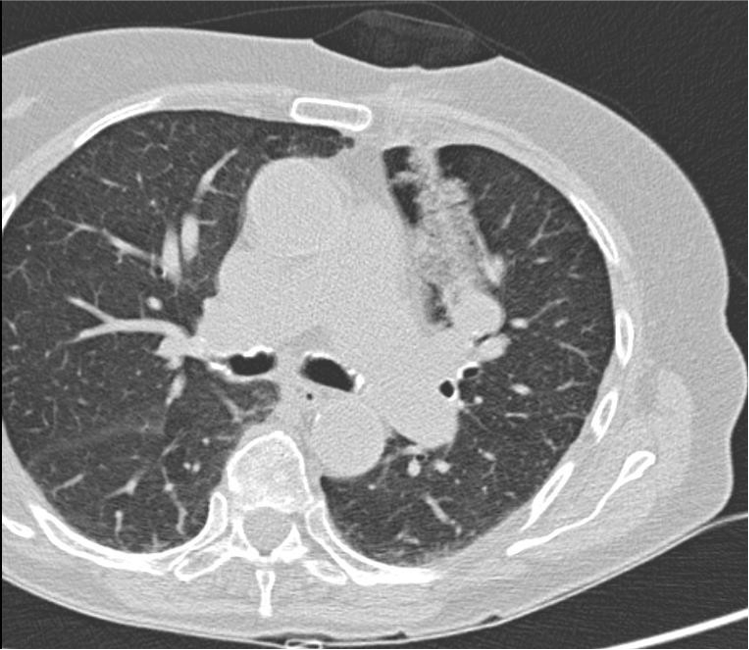

怀疑宫颈癌肺转移

病理证实:慢性感染

肺门结节

肺动脉造影证实左肺门结节(不是肺动脉)

后入路有肩胛骨,水平入路考虑病变后方为主动脉,仅经胸骨旁入路相对安全,需要避开乳内动脉,和结节后方的肺动脉和支气管。此病例活检相对风险

第一次CT扫描:观察引导针穿刺的方向和平面是否和靶病变一致(注意穿刺针的针尖不能停留在脏层胸膜表面,避免气胸)

第二次CT扫描:观察穿刺针在肺内的方向与平面是否与靶病变一致(注意每次针前进的距离是剩余针道的一半,以便随时纠正穿刺针前进的方向和水平)

引导针到病变的边缘

置换活检针

活检针进入病灶内活检,注意后方,针尖不要超过病灶的后界

拔针后显示沿针道少量肺实质出血